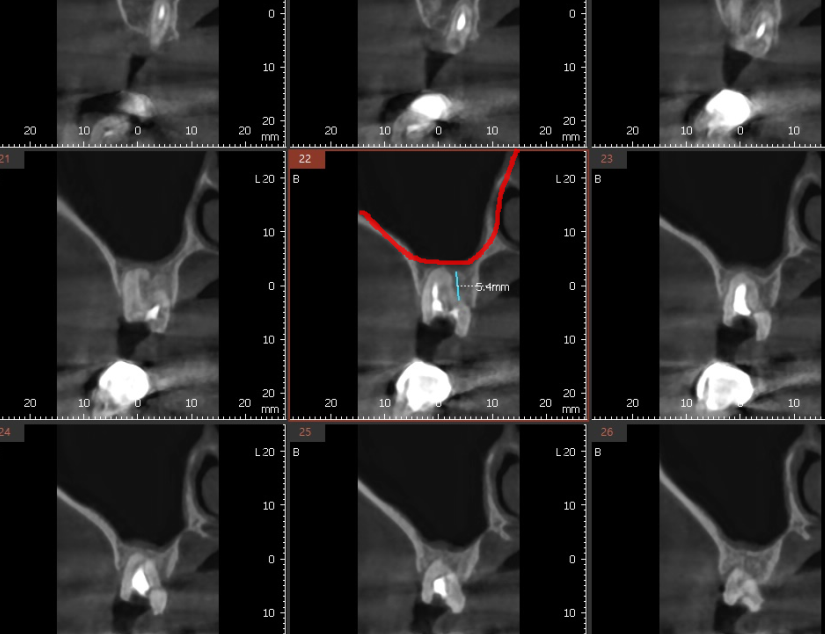

수술 진단 시 문제가

상악동과 근접한거였는데요.

임플란트 길이가 5.4mm정도 부족한 것은

상악동 거상을 동반한 뼈이식으로 해결하였습니다.